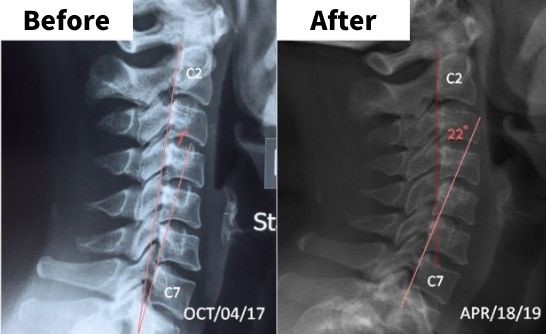

✔ iTrac®頸椎治療技術提供超過55種不同設置,為不同患者的頸椎狀況制定個人化治療方案,修復頸椎至自然的生理弧度

治療前後對比圖